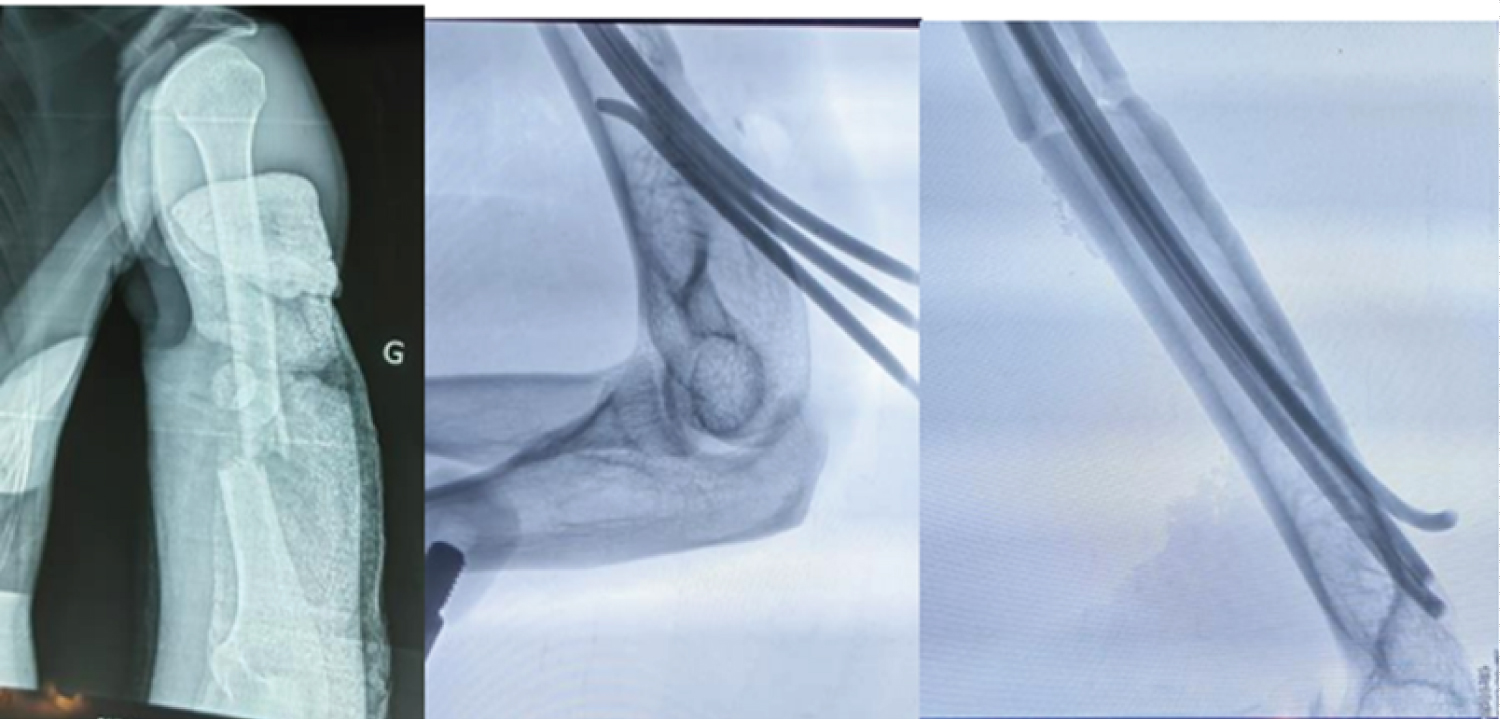

We conducted a descriptive cross-sectional study over a 54-month period from January 2019 to June 2023 at the Orthopedic and Trauma Surgery Department (SCOT) of the Renaissance University Hospital. All patients aged 18 or over who underwent surgery and were followed up at SCOT during the study period and had a usable clinical record were included. Patients treated by other surgical procedures and orthopedically, as well as those with incomplete clinical records, were excluded from our study. The AO classification was used for bone lesions and the Gustillo/Anderson (G/A) classification for skin opening. All patients were positioned supine on a standard table under general anaesthesia, with the fractured limb placed on a radiolucent table. Reduction was performed by external maneuvering under the control of a mobile image intensifier, parallel to the operating table. The supra-olecranial approach through an oval hole was used to insert Metaizeau wires of various sizes (Figure 1). The pins were inserted into the fracture site and diverged in the humeral head under image intensifier control (Figure 2), and an immediate control radiograph was taken (Figure 3). Epidemiological, radio-clinical, therapeutic and evolutionary variables were studied on the basis of a data sheet and patient summons. Anatomical and functional results were assessed using the STEWARD AND HUNDLEY score.

Figure 2: (a) Left humeral shaft fracture; (b) Wire insertion. View Figure 2

Figure 3: Control X-ray (a) front (b) profile. View Figure 3